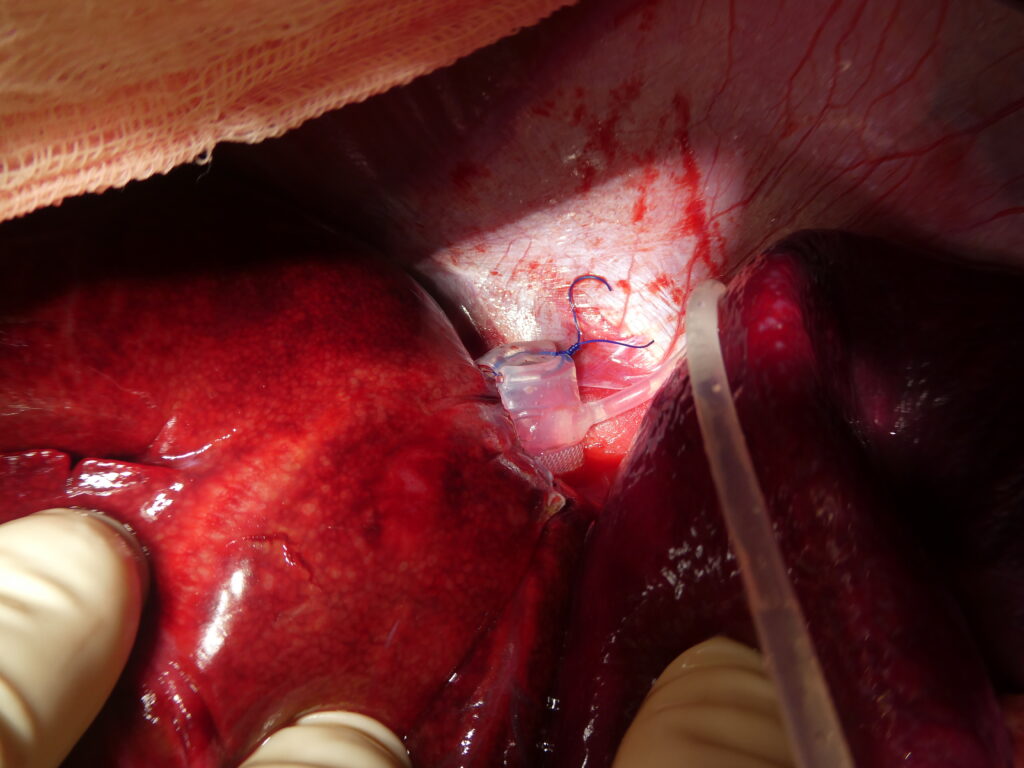

Chirurgie d’un shunt porto-systémique intra-hépatique complexe.

Au centre, mise en place peropératoire d’un obturateur hydraulique directement sur le shunt, permettant une occlusion contrôlée du flux anormal.

À droite, implantation de la chambre d’accès sous-cutanée, utilisée pour gonfler progressivement l’obturateur hydraulique et obtenir une atténuation graduelle du shunt, afin de limiter les risques physiologiques liés à une occlusion brutale.